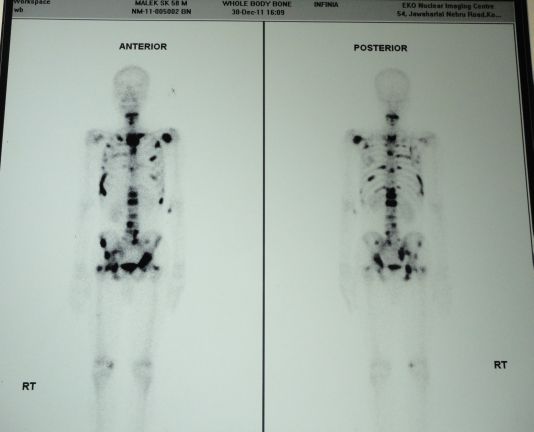

Adenocarcinoma and squamous cell carcinoma are the most frequently diagnosed histological subtype of bronchogenic carcinomas. Though metastatic lesions in lung are common in both the varieties, cavity formation has been documented only with squamous cell type. Here we are going to report a case of pulmonary adenocarcinoma with multiple nodular metastases in both lungs which show central necrosis mimicking cavities.